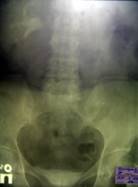

Контрольное обследование, произведенное в апреле 2006 года (через 12 месяцев после нефрэктомии и, соответственно, через 7 месяцев после пластики рецидивного ПВС), не обнаружило признаков рецидива онкопроцесса. При вагинальном осмотре определяется опущение передней стенки влагалища, на нисходящей урограмме - опущение мочевого пузыря (Рис. 3). Жалобы на какое-либо нарушение акта мочеиспускания отсутствуют. В общем анализе крови: содержание гемоглобина - 150 г/л, СОЭ - 4 мм/час. Впервые выявлен сахарный диабет.

Рис. 3. Выделительная урограмма с нисходящей цистограммой.